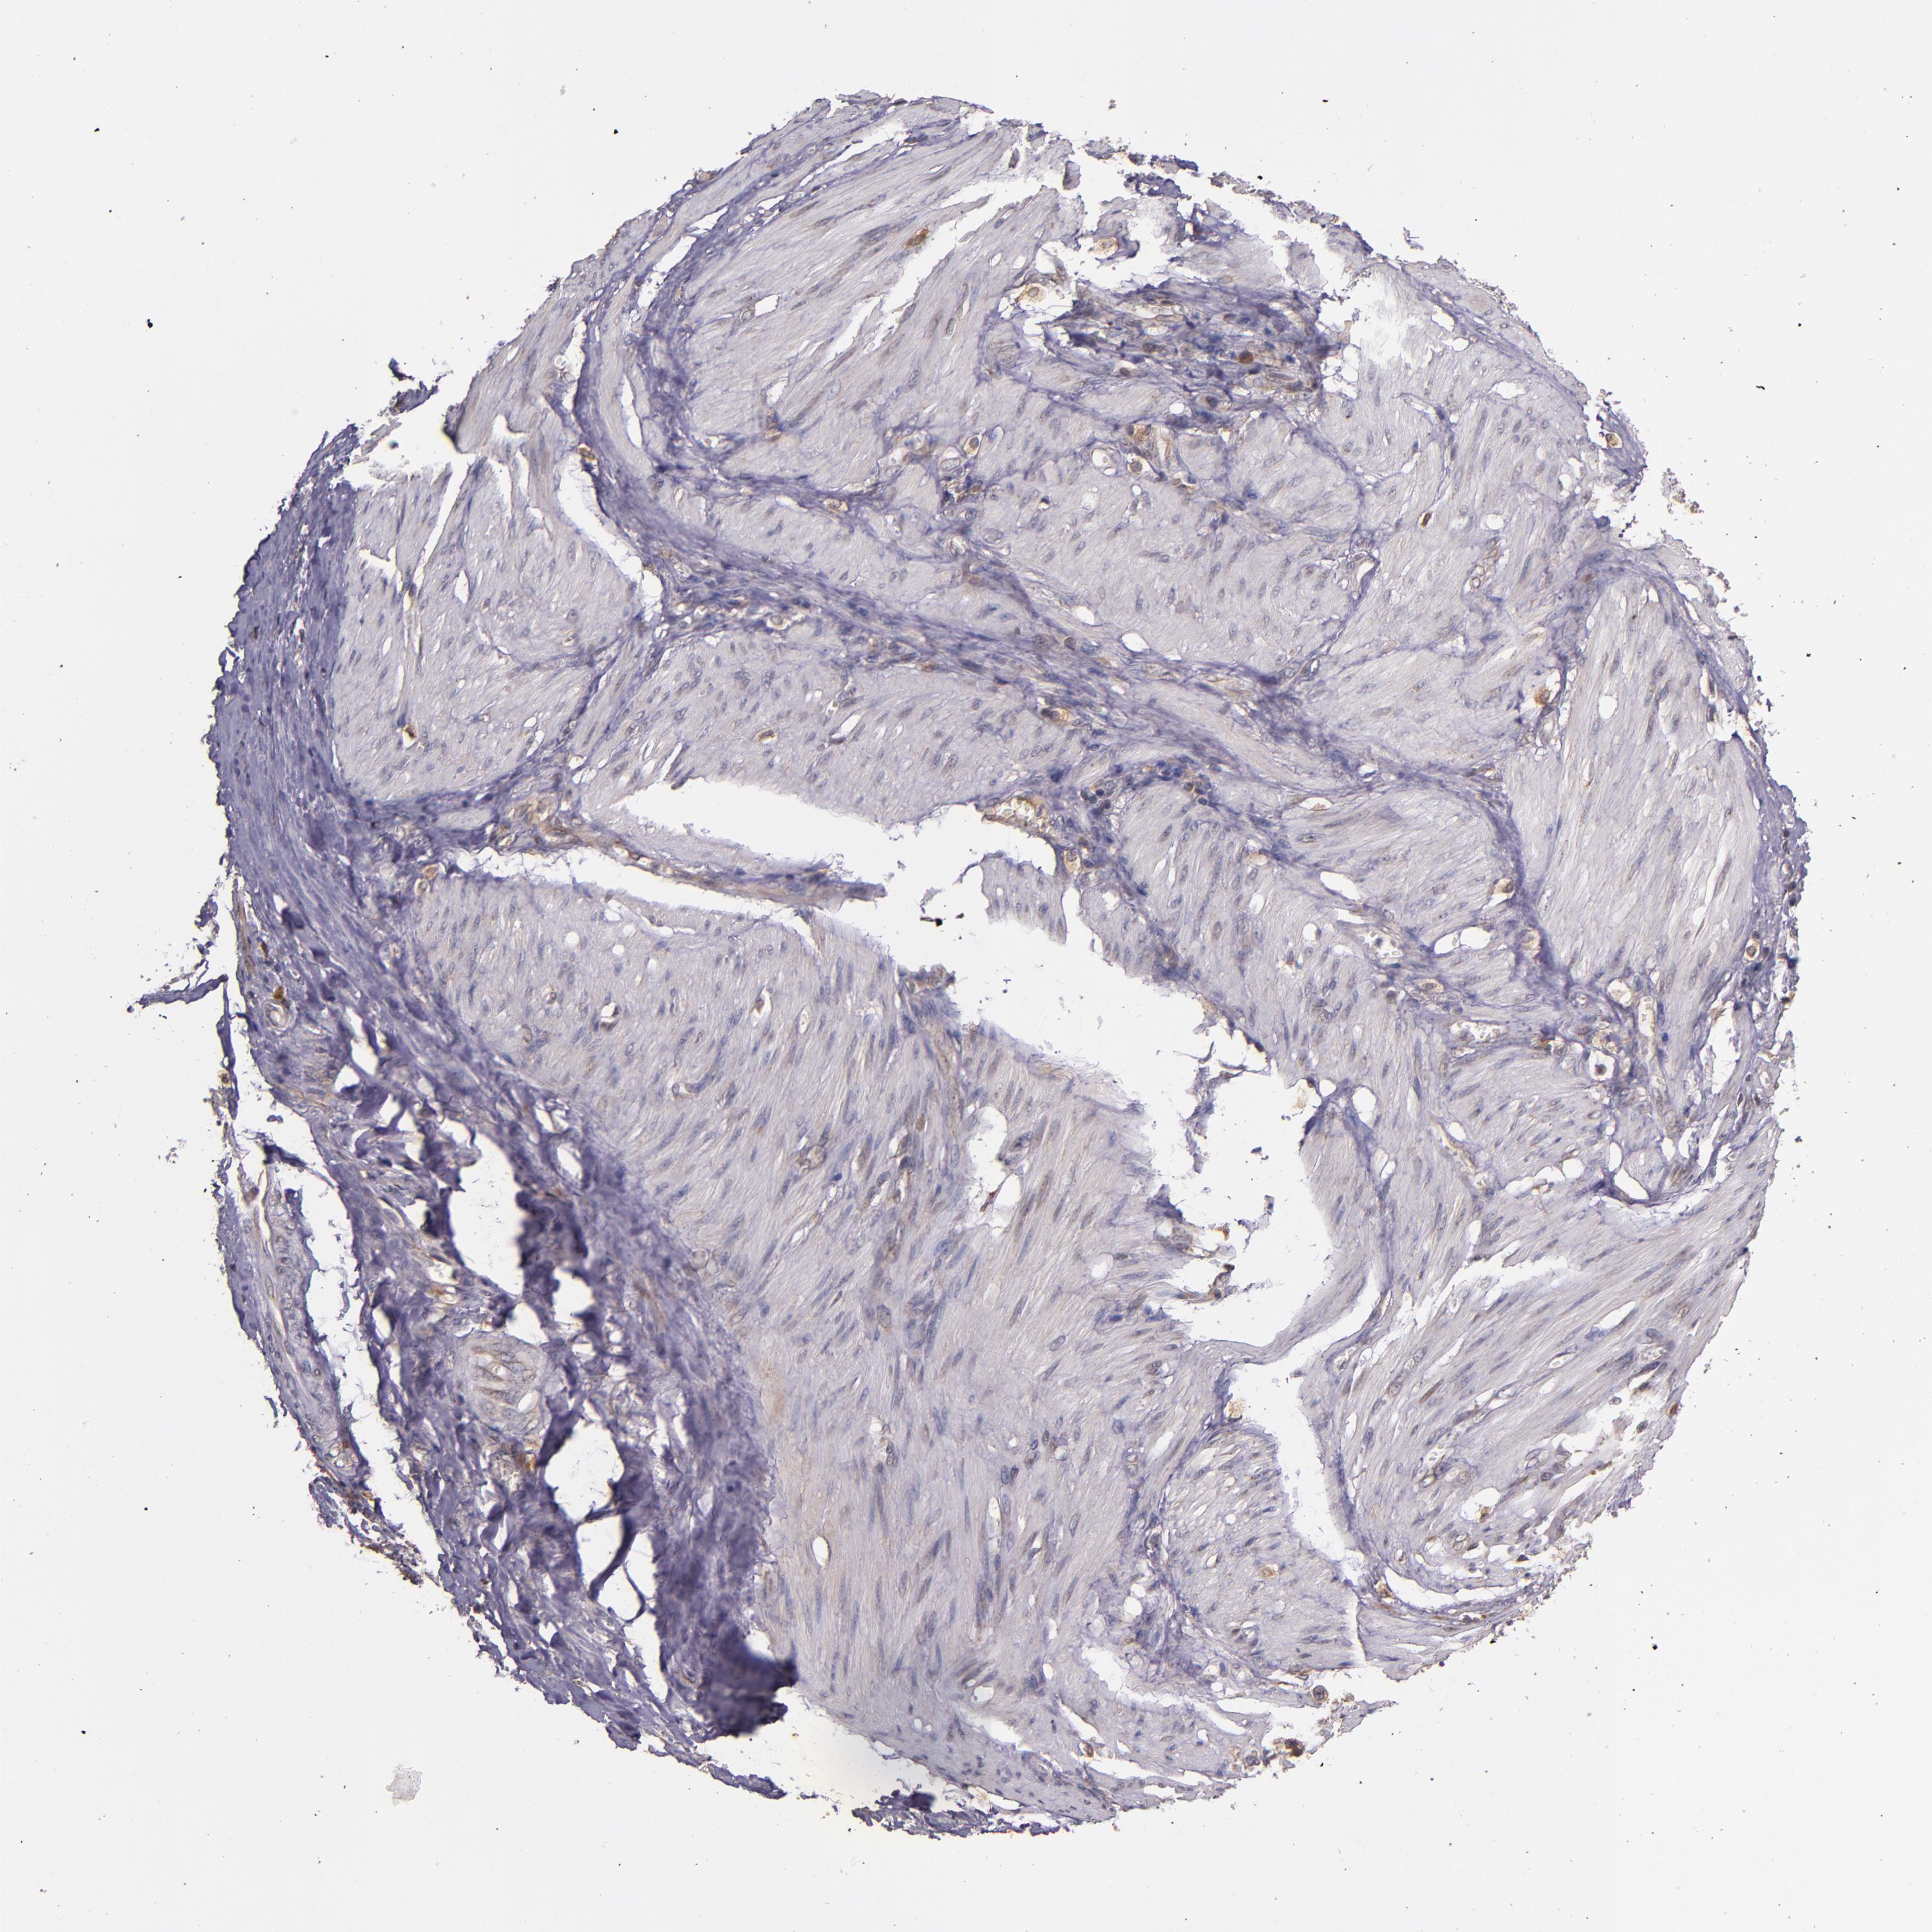

STOMACH CANCER - Protein expressioni

A mouse-over function shows sample information and annotation data. Click on an image to view it in a full screen mode. Samples can be filtered based on level of antibody staining by selecting one or several of the following categories: high, medium, low and not detected. The assay and annotation is described here.

Note that samples used for immunohistochemistry by the Human Protein Atlas do not correspond to samples in the TCGA dataset.

Antibody stainingi

Antibody staining in the annotated cell types in the current human tissue is reported as not detected, low, medium, or high, based on conventional immunohistochemistry profiling in selected tissues. This score is based on the combination of the staining intensity and fraction of stained cells.

Each image is clickable and will lead to virtual microscopy that enables deeper exploration of all samples and also displays staining intensity scores, fraction scores and subcellular localization as well as patient and tissue information for each sample.

Antibody HPA002859

Antibody CAB011655

Staining

High

Medium

Low

Not detected

Intensity

Strong

Moderate

Weak

Negative

Quantity

>75%

75%-25%

<25%

None

Location

Nuclear

Cytoplasmic/membranous

Cytoplasmic/membranous,nuclear

Adenocarcinoma, NOS

Adenocarcinoma, High grade